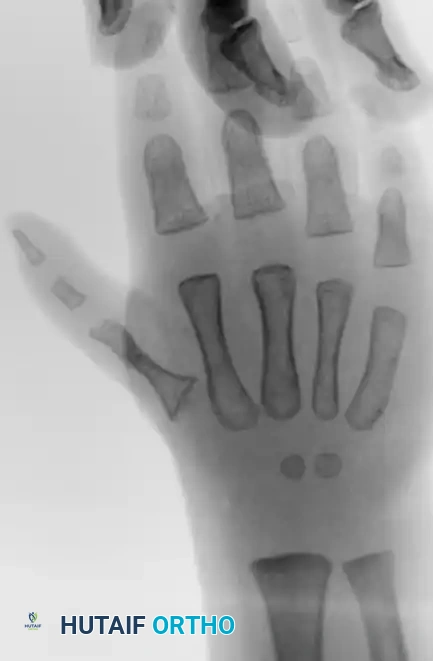

Preoperative radiograph of a child with thumb hypoplasia, illustrating the skeletal deficiencies that often accompany the soft-tissue imbalances seen in clasped thumb deformities.